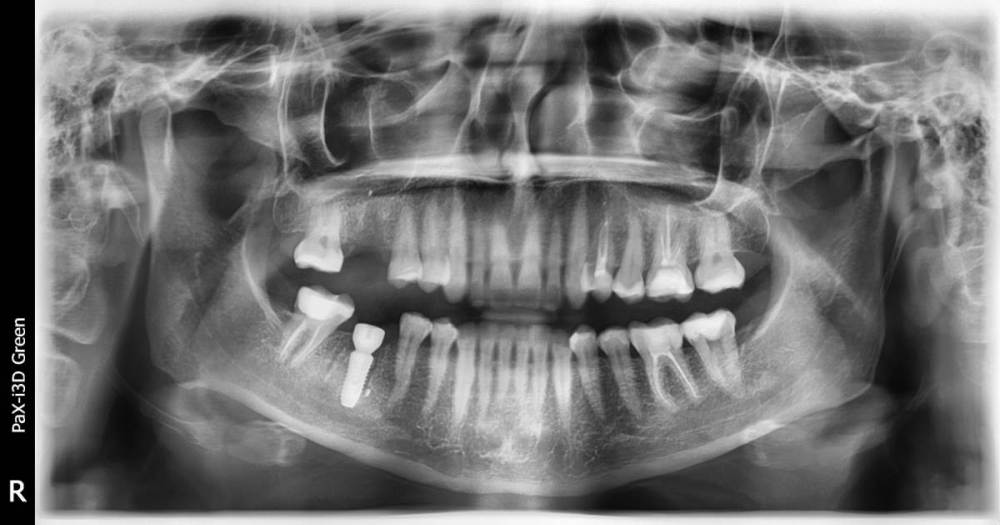

Yana-Anny Опубликовано 11 апреля, 2021 Поделиться Опубликовано 11 апреля, 2021 6 дней назад сделала одномоментную имплантацию (46-й зуб, удалять пришлось из-за сильно выведенного за пределы корня пломбировочного материала и болей). После удаления доктор извлек пломбировочный материал, установил имплант, засыпал в лунку костную крошку, заложил плазму из крови и наложил швы. На шестой день боль и отек не спадают, доктор говорит, что все в пределах нормы. Но боль сильная, обезболивающими не снимается полностью. Может ли быть задет нерв? Может ли такие боли давать зуб зуб рядом? По КТ воспалений нет, но он депульпирован и на нем большая пломба. Понимаю, что без снимков сообщение неинформативно, снимки не дали (сказали, что боль может продолжаться до двух недель и должна быть терпимая, меньше думать о ней побольше отвлекаться) Ссылка на комментарий

Yana-Anny Опубликовано 22 апреля, 2021 Автор Поделиться Опубликовано 22 апреля, 2021 (изменено) Удалось выпросить снимки, но боль практически утихла уже, только немного ноет челюсть. Посмотрите, пожалуйста, еще 26 зуб, диагноз гранулема на верхушке корня. Проведена ревизия каналов, временное пломбирование пастой каласепт, затем постоянное гуттаперчевыми штифтами. Постпломбировочные боли 4-й день довольно сильные. Есть ли шанс спасти зуб? Изменено 22 апреля, 2021 пользователем Yana-Anny Ссылка на комментарий

red_butler Опубликовано 22 апреля, 2021 Поделиться Опубликовано 22 апреля, 2021 по снимкам все нормально. 2.6 нужно на Кт посмотреть 1 Ссылка на комментарий